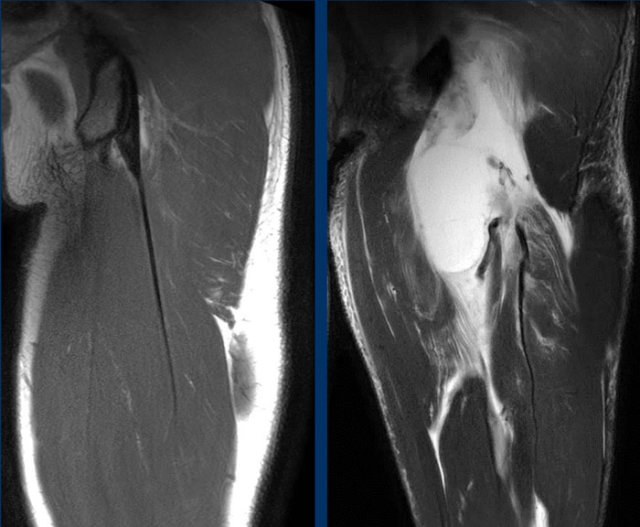

Full thickness injury

Free tendon tear

In full thickness injuries, the free tendon is torn and  discontinuous with the ischial tuberosity.

Since tension is lost, the tendon and muscle will retract from the tuberosity and a gap is seen.

The extent of tendon retraction or is considered an important factor for treatment decision-making.

Some experts advocate surgical repair when retraction is more than 2 centimeters.

Direct measurement of retraction

The most reliable method to quantify retraction is the ‘direct measurement’ on a coronal fluid-sensitive sequence.

First, the point representing the center (white triangle) of the proximal hamstring complex origin on the upper region (dotted line) of the ischial tuberosity (IT) is determined.

From this point, the direct (ie, shortest) distance (white arrow) to the most proximal part of the hypointense tendon stump (black triangles) is measured (in cm).

Note that determining the anatomic landmarks is done on different images within one MRI sequence.

On these images a full thickness injury is seen.

Both scoops have dropped on the axial images, so both tendons are avulsed.

On coronal images total retraction was measured and noted.

Reinsertion

After a full thickness avulsion, tendons can be reinserted operatively. In this case, the anchors at the tuber can be seen. As a result from the injury, fatty atrophy of the muscle belly can occur.